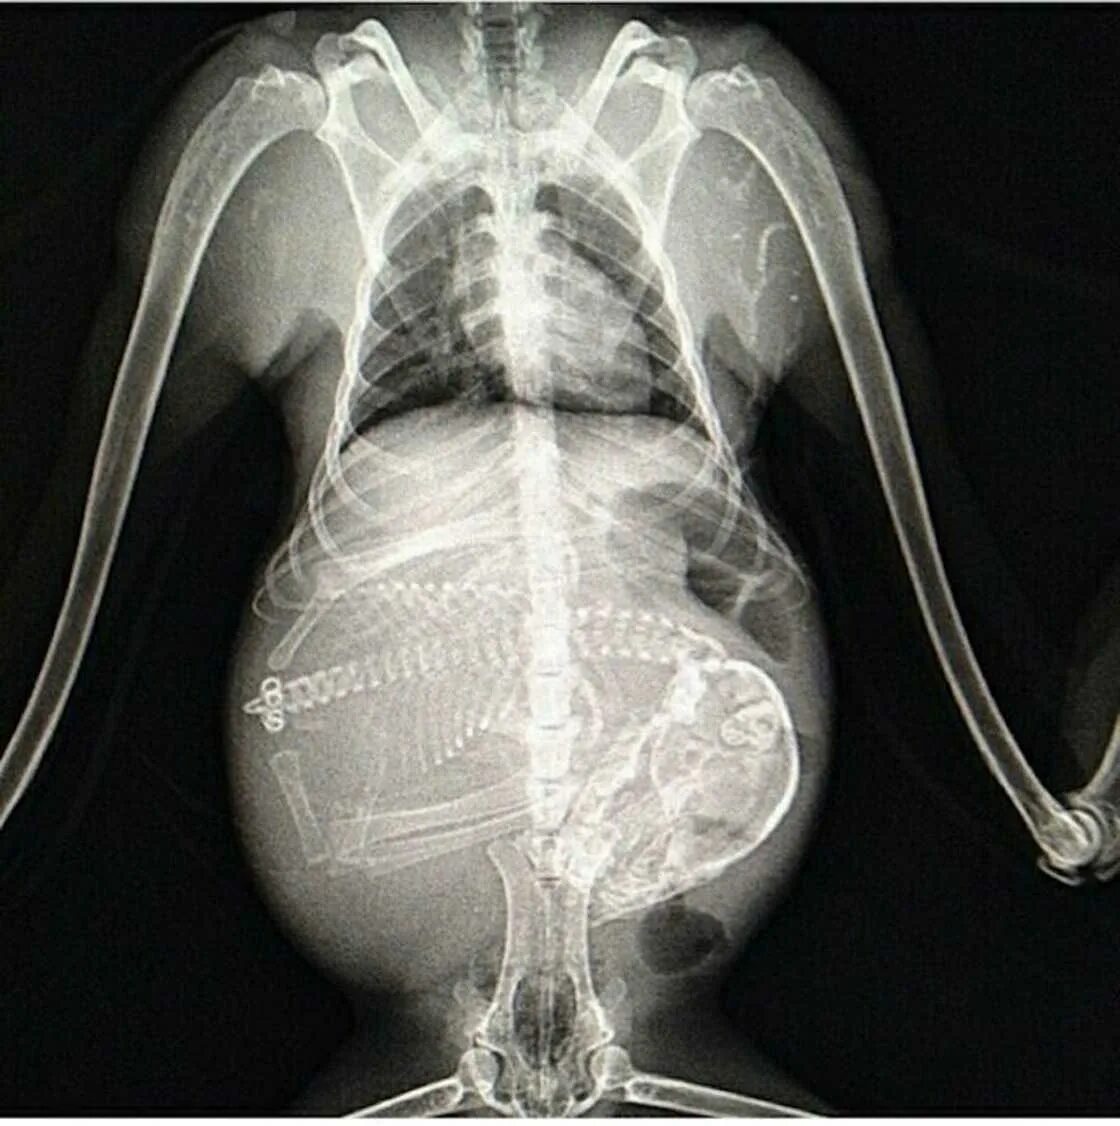

Делала рентген при беременности